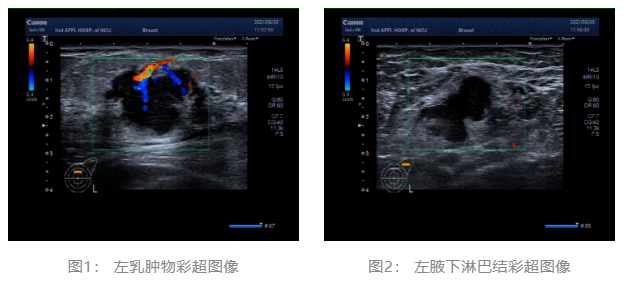

2021.06.30乳腺体层成像:双乳ACR c型。左乳肿块,BI-RADS 4C 类。双乳腺体增生样改变,BI-RADS 2类。(图3、4)

▌乳腺体层成像: